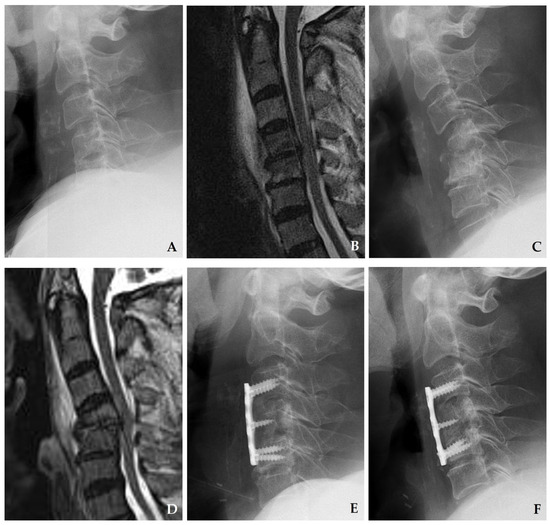

Figure 6. Initial plain radiograph (A) and magnetic resonance imaging (MRI) (B) demonstrate disc space narrowing at C4–C5 with a retropharyngeal abscess. After one month of antibiotic treatment, follow-up plain radiograph (C) and MRI (D) reveal progressive destructive changes in the C4–C5 vertebral bodies with kyphotic deformity, accompanied by retropharyngeal and epidural abscesses compressing the spinal cord. The patient underwent C3–C5 corpectomy with autograft and anterior plating (E), achieving solid fusion and complete resolution of spondylodiscitis at one year postoperatively (F).